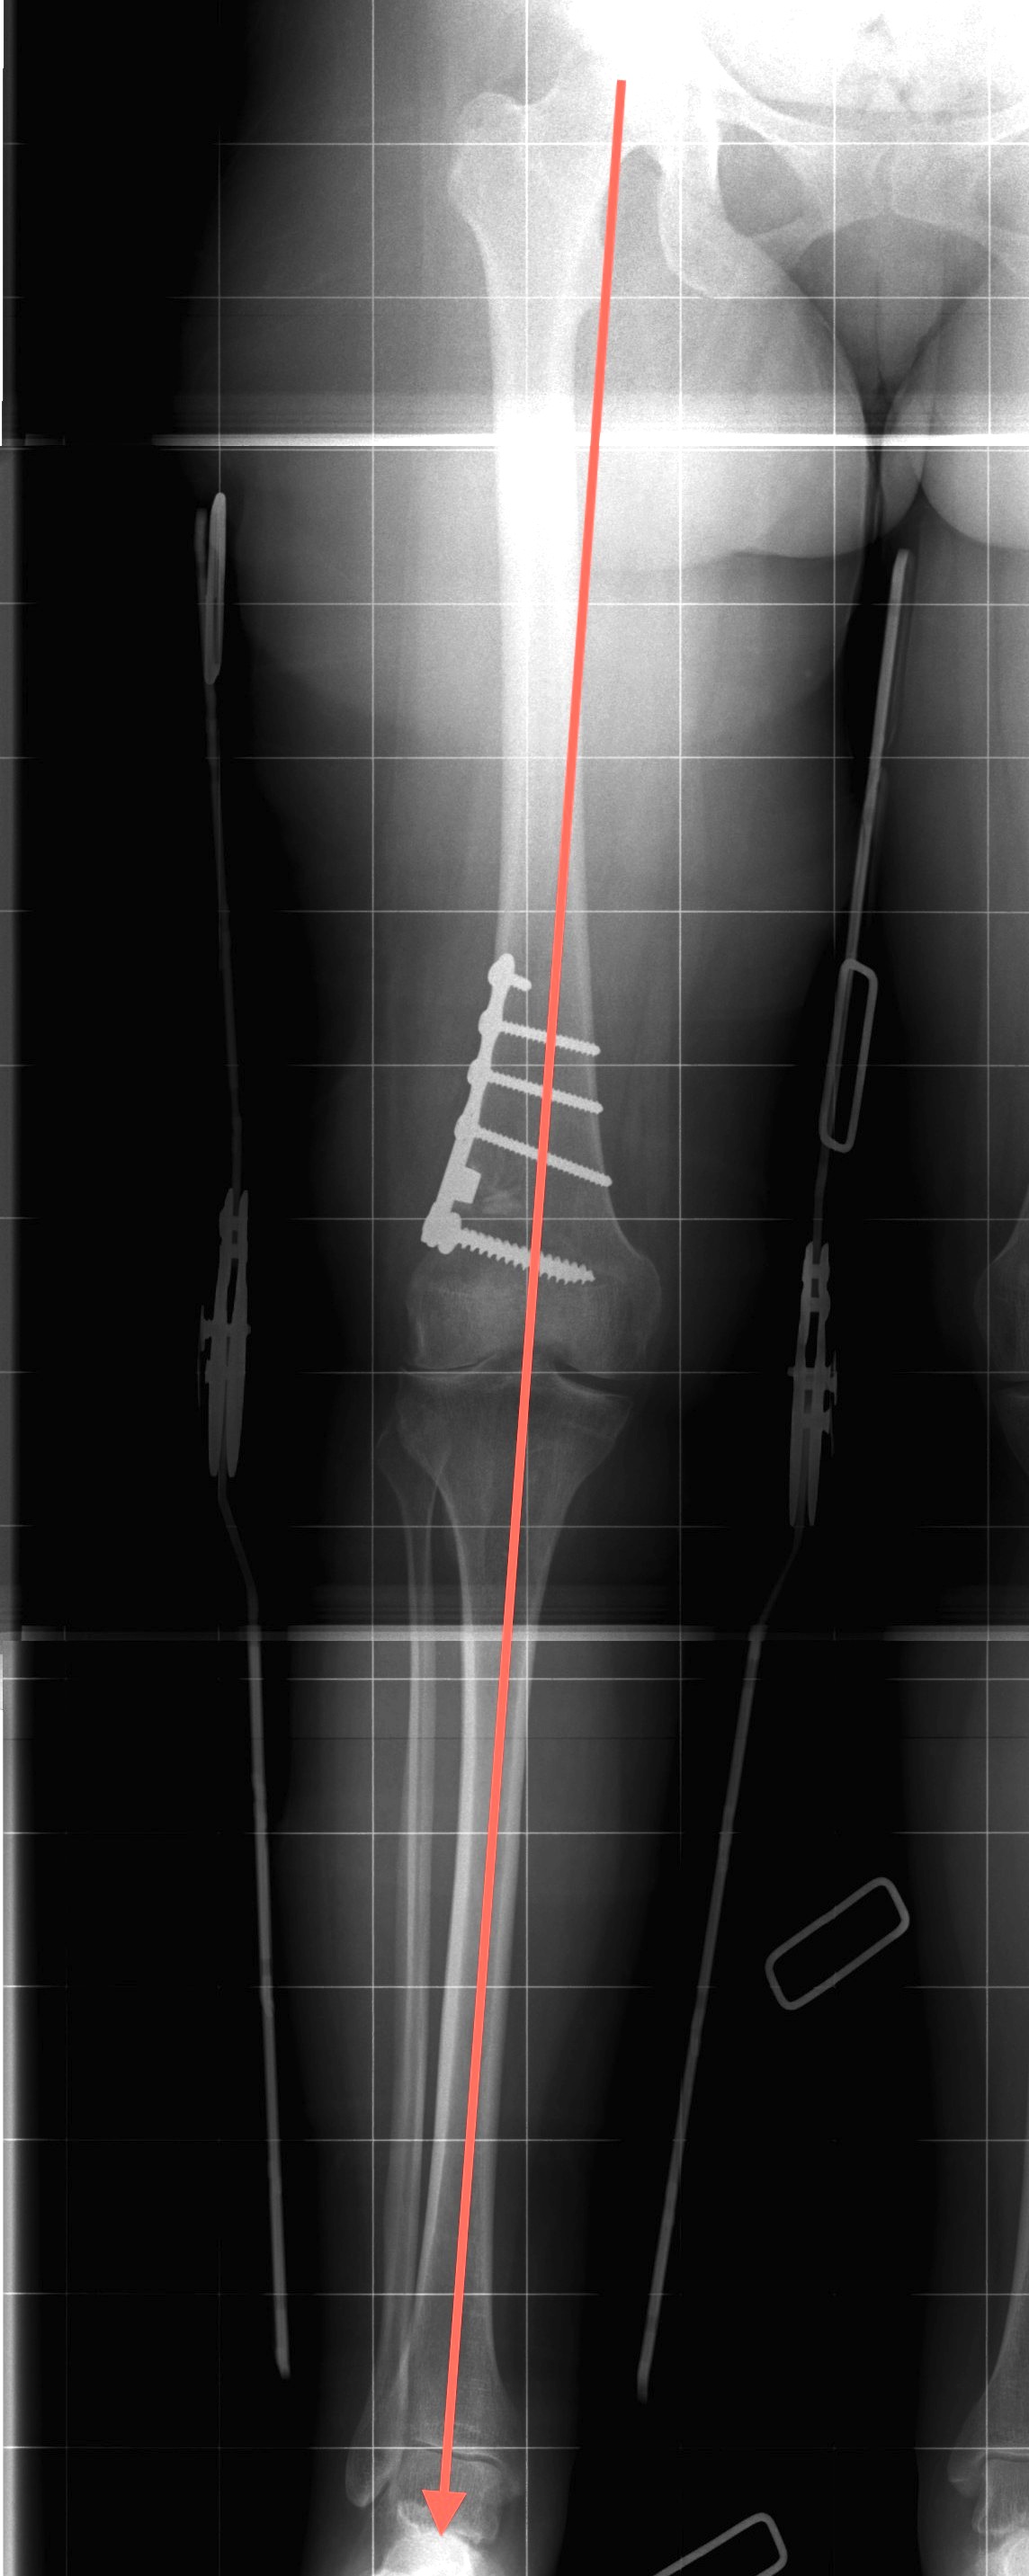

Preoperative Planning

AP full length standing xrays

Line from centre of talus to desired mechanical axis

Line from centre of femoral head to desired mechanical axis

a) is the desired angle of correction